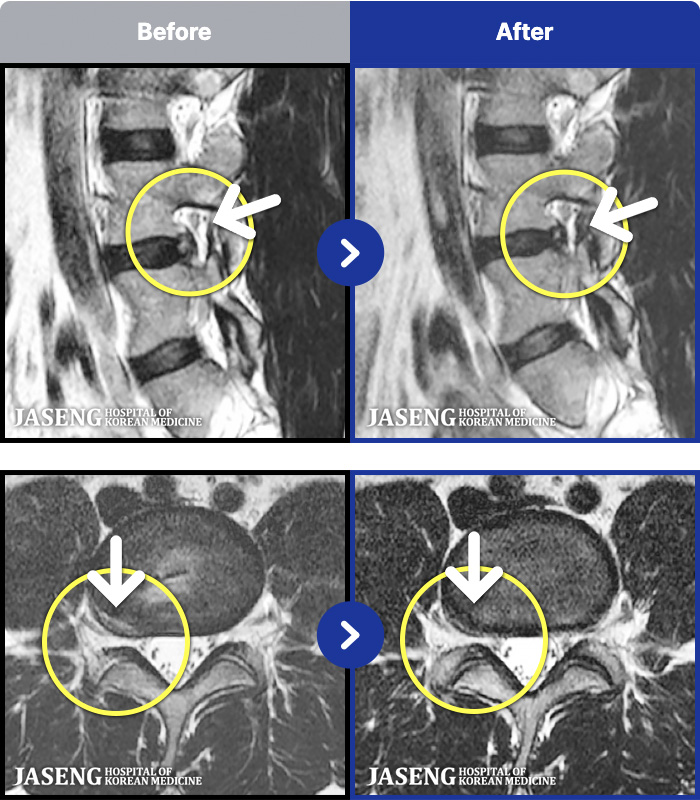

191 MRI ũ ʸ Ȯϼ.

ȯںп Ǹ ǿ ԿǾ, ο ġ ۿ Ƿ ġḦ Ͻñ ٶϴ.